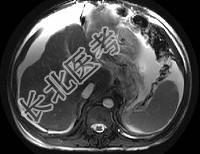

- 单项选择题男,44岁, 有乙肝病史,现腹胀, 右上腹痛,消化不良, 消瘦、乏力、贫血、黄疸,血清转氨酶升高, 清蛋白/球蛋白比值倒置。CT、MRI检查如下图,最准确的诊断是 ( )

A、肝硬化并腹水

B、肝硬化并腹水、再生结节

C、肝硬化腹水、肝癌

D、肝硬化并再生结节

E、肝硬化并腹水、脂肪肝